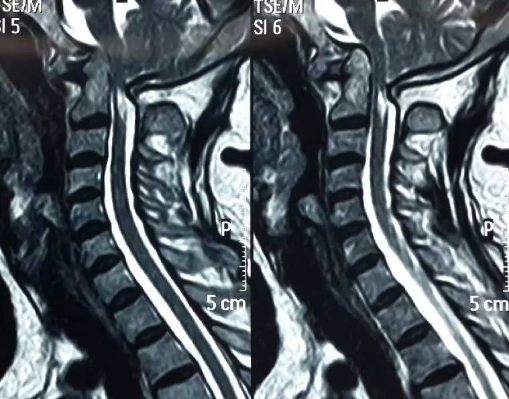

3影像学检查

手术前后伸前屈位X光片寰枢椎脱位为可复性(后伸位脱位复位,前屈位寰齿前间隙(ADl)大于5mm)。寰枢椎CT椎弓根发育良好(大于4mm),磁共振脊髓损伤伴椎管狭窄。

手术前前屈位X光片寰枢椎脱位(寰齿前间隙7mm)。寰枢椎三维CT见寰枕融合,颅底陷入(齿状突位于钱氏线上14.2mm),右侧枢椎椎弓根发育狭小(小于2mm),磁共振显示小脑扁桃体下疝、颈髓损伤伴椎管狭窄。